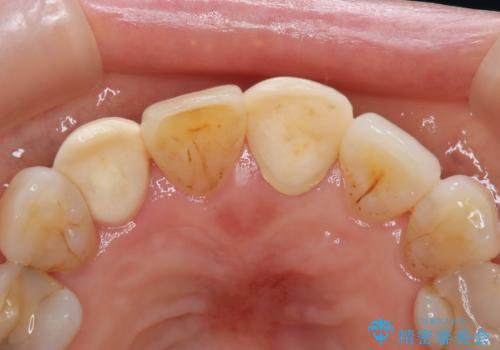

【外傷歯】根管治療から被せ物まで。

- 外傷により他院で治療中に転院を希望され受診されました。

前医では、抜歯も提案をされていましたが適切に治療を行うことで歯を保存することができました。

歯槽骨内水平性歯根破折は、抜歯の適応ではありません。